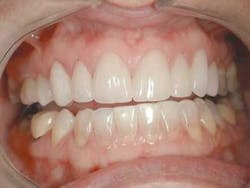

The final result of this case sees an improvement in all of the original objectives (Figs. 12, 13, 14). Our patient wanted a lighter, wider smile that would cover the darkness she had lived with her entire life. Needless to say, she was ecstatic with the end results (Figs. 15, 16).

null